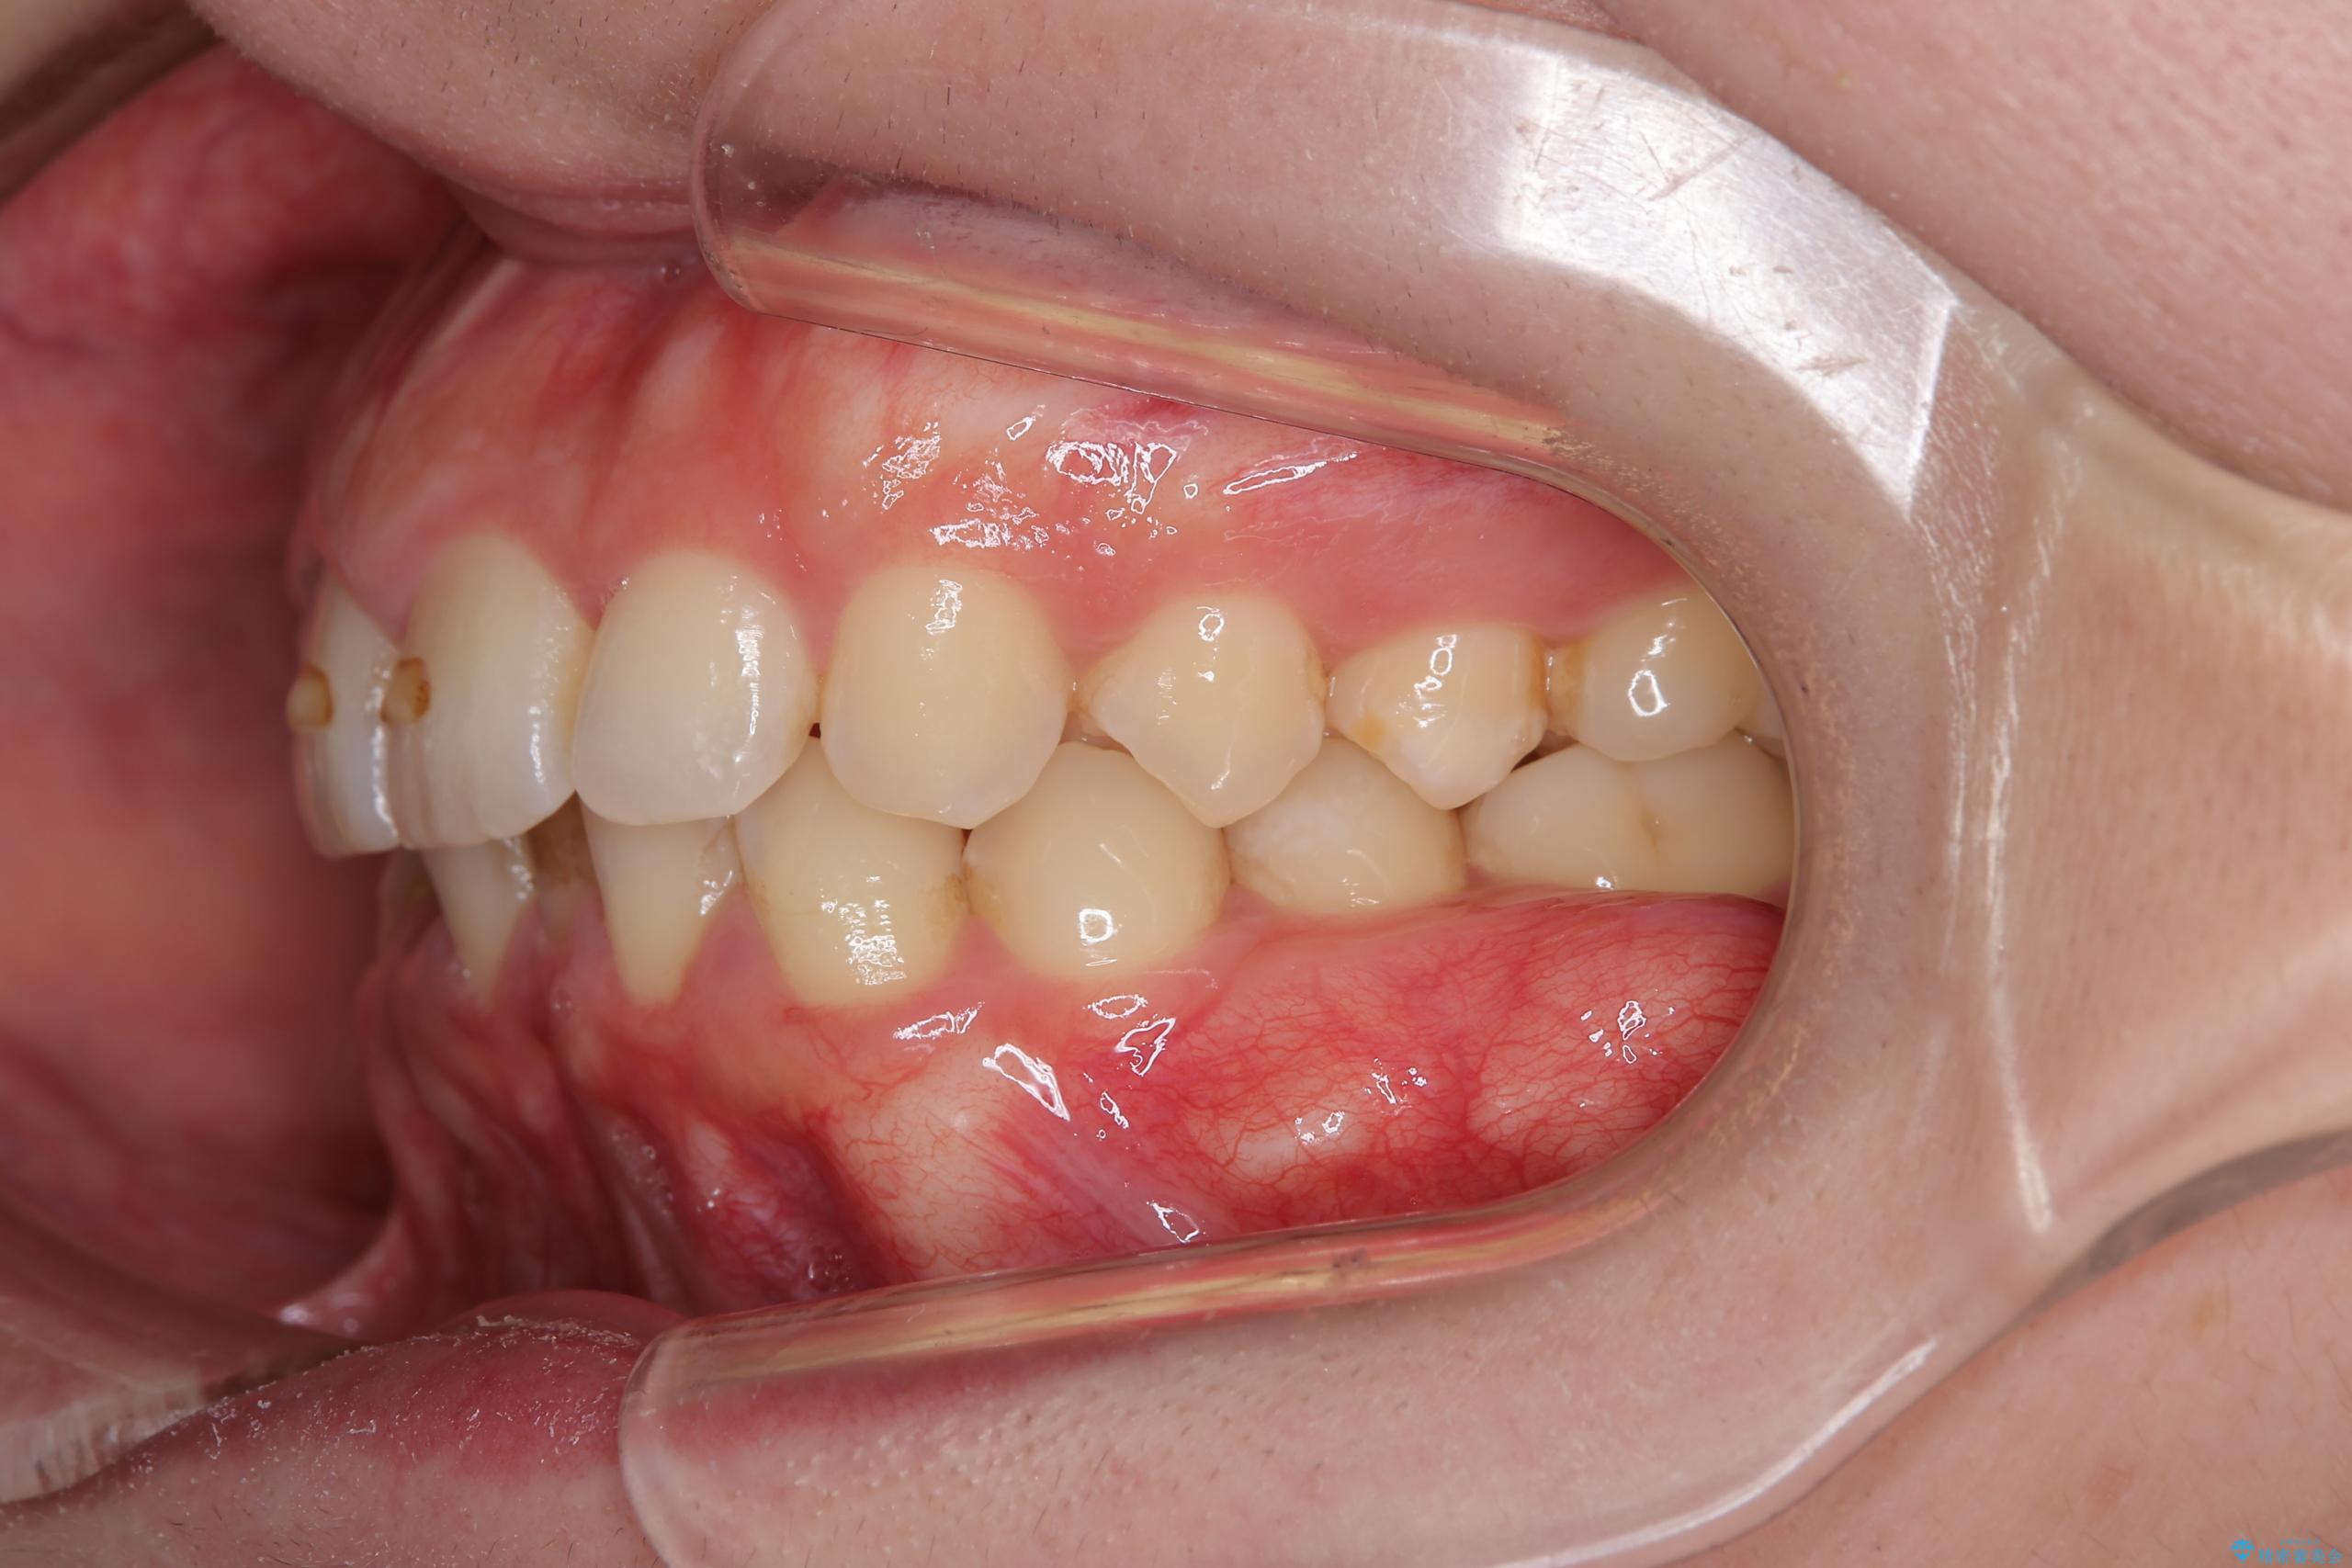

- 下の歯のがたつきを主訴に来院されました。

下の歯のがたつきと右の奥歯の噛みあわせ改善するために治療計画を立てることにしました。

右側臼歯部の咬合改善のために、臼歯部のみ部分的なワイヤー矯正を行い、咬合改善がみられてからインビザラインにて全体的な矯正を行なっていく治療計画を立てました。

噛み合わせをよくするために、ワイヤー矯正とインビザライン矯正のどちらの期間も必要な箇所にゴム掛けを行いながら治療を行いました。

ゴム掛けを頑張っていただいたので、噛みあわせも改善され綺麗な歯並びになりました。